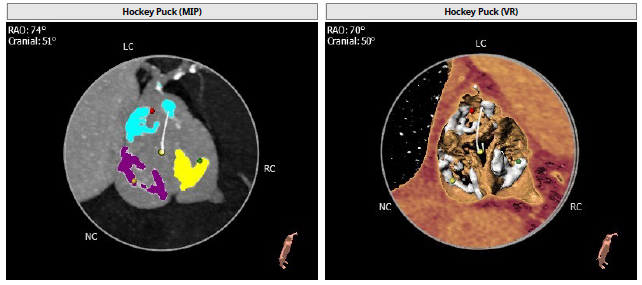

根部解刨

患者为三叶瓣,重度钙化,瓣环29.1 mm,LVOT28.6 mm,预计瓣口开口29.1 mm,STJ 32.3 mm,窦部空间大,左右冠高度分别为16.2 mm和19.8 mm,预计24mm球囊预扩。